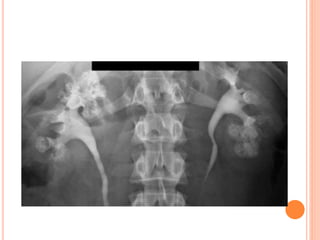

INTERMEDIATE FILLING

Vesicoureteral reflux can be

seen on oblique radiographs

obtained just before voiding

and can be graded after

voiding with the International

Reflux System.